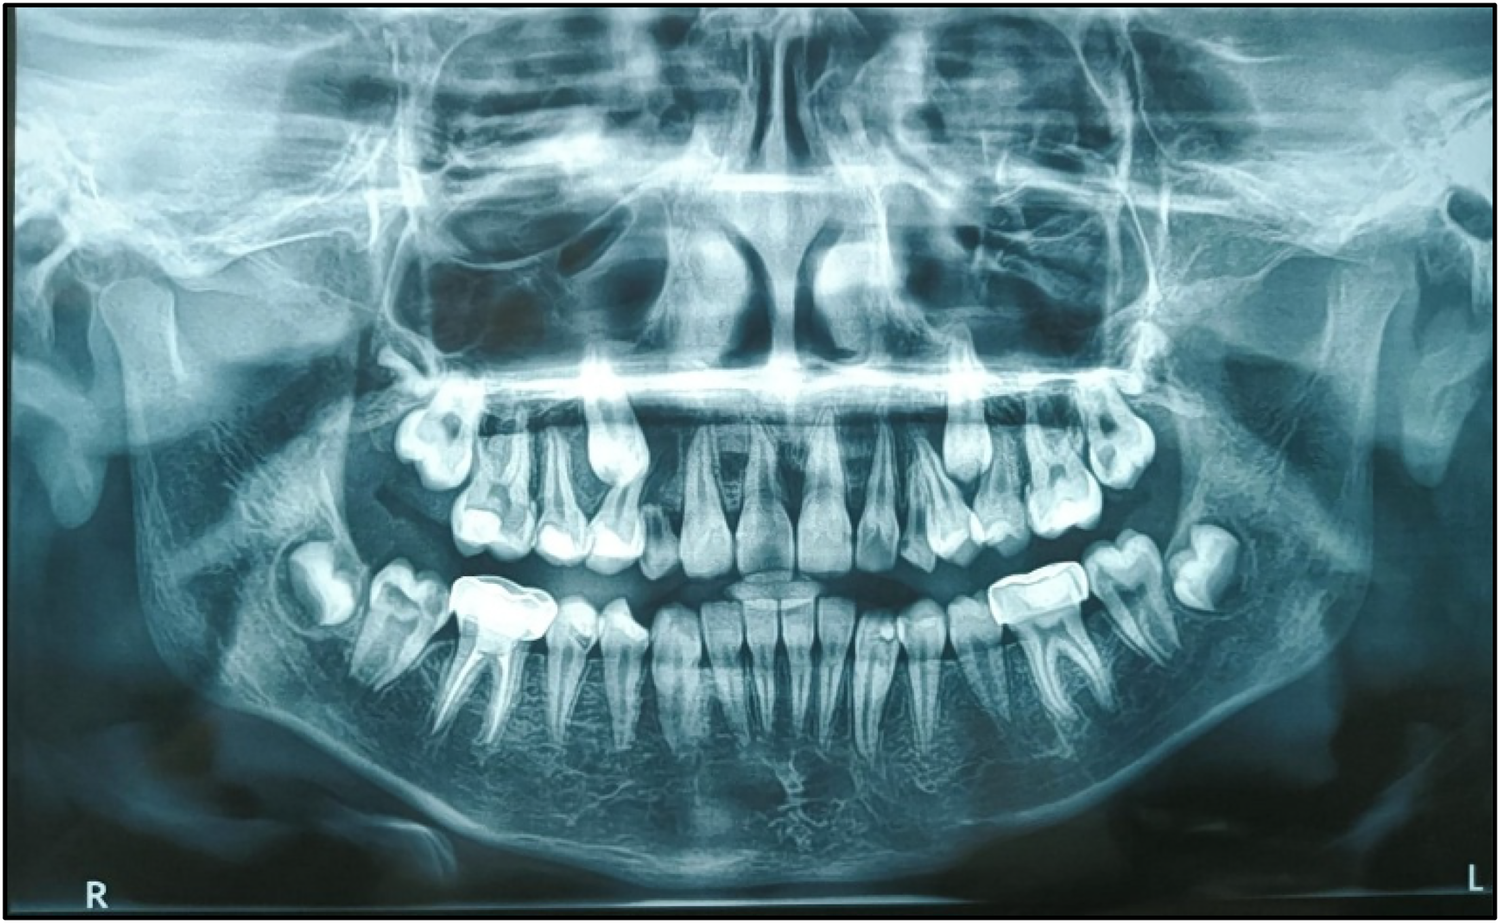

A meticulous post-treatment follow-up was conducted. During the initial follow-up visit, an OPG was advised (Figure 5), which revealed a radiolucency in the region of teeth 13 and 14. To further evaluate and rule out any underlying pathology, a Cone Beam Computed Tomography (CBCT) scan of the 13, 14, 15 region was advised (Figure 8). CBCT findings revealed no pathological changes in the specified region; however, transposition of teeth 13 and 14 was noted (Figure 6).

Follow-up is a critical component in the management of such cases. A 3-monthly follow-up protocol was implemented for the teeth affected by PEIR until complete eruption, followed by appropriate treatment. Subsequent follow-ups were scheduled every 3 months, tailored to the patient's individual caries risk assessment (as per CRAFT recommendations) (Figure 9).